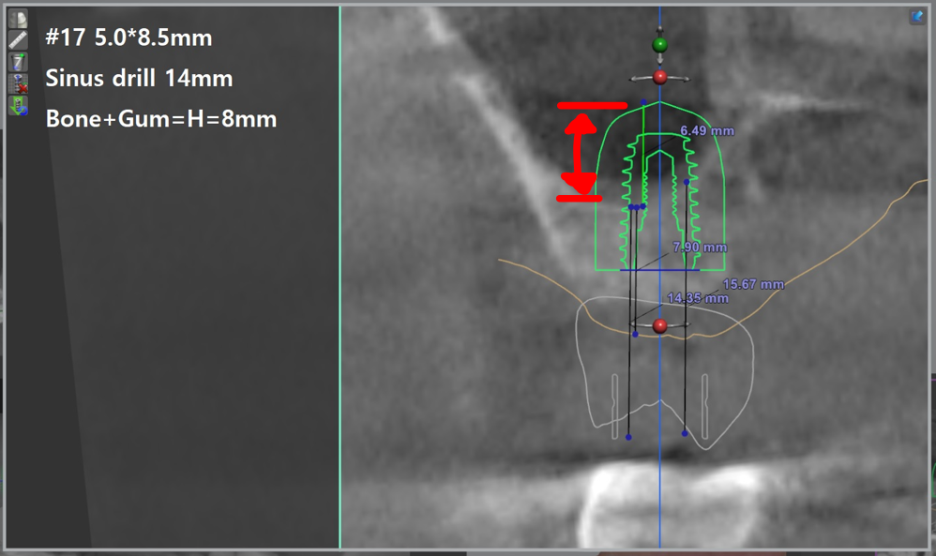

『컴퓨터 시뮬레이션 진행

조금 더 정확하게!』

컴퓨터 단층 촬영(CT)를 통해서 조금 더 정확하게 상악동 까지의 거리를 측정하면서

심겨지는 임플란트 길이와 함께 얼마 만큼의 거상술 을 진행해야되는지 살펴봅니다.

화면에서 보실 수 있는 3D 모형은 디오나비 라는 디지털임플란트 시스템 구현 화면입니다.

미리미리 시술 결과를 예측할 수 있는 스마트한 기술이죠.

이 과정에서 염증이 있다는 것 또한 알아낼 수 있었습니다. 조금 더 시술을 하는데

도움이 되는 정보들을 한 눈에 술자에게 알려주기 때문에 예후가 좋을 수 밖에 없겠죠.

또한, 미리 어떤 형태의 보철이 올라가야 되는지도 예측을 할 수 있습니다.